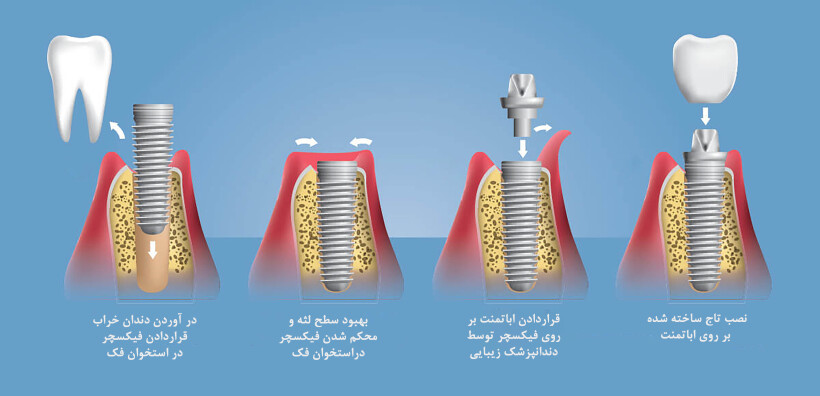

قبل از هرچیز بهتر است به طور مختصر به تعریف خود ایمپلنت بپردازیم. ایمپلنت در لغت به معنی کاشت است. در دندان پزشکی از روش ایمپلنت یا کاشت دندان برای پر کردن جای خالی دندانهای از دست رفته استفاده میشود. گاهی اوقات ممکن است دندانها بر اثر ضربه شدید، پوسیدگیهای عمیق، بیماریهای لثهای، عفونت و... از بین بروند. در چنین مواردی کاشت دندان یا ایمپلنت بهترین روش برای جایگزین کردن این دندانهاست. زیرا پایه ایمپلنت که در استخوان و لثه قرار میگیرد از جنس تیتانیوم بوده که کاملاً با بدن سازگار است و با مقاومت بسیار بالایی که دارد میتواند وظیفه ریشه دندان را به عهده بگیرد.

کاشت ایمپلنت دندانی یکی از ظریفترین و حساسترین کارهایی است که باید حتماً توسط یک جراح دندان حرفهای وبا تجربه انجام شود. زیرا هرگونه بی دقتی در کاشت پایه ایمپلنت موجب آسیب رساندن به استخوان فک بیمار خواهد شد. زمان تکمیل درمان ایمپلنت نیز تا حد زیادی به شرایط سلامتی بیمار بستگی دارد. در حالت نرمان پایه ایمپلنت(فیکسچر) در یک جلسه انجام میشود و بیمار پس از دوماه برای روکش ایمپلنت اقدام میکند مراحل انجام ایمپلنت به شرح زیر است:

1.جلسه اول معاینه و بررسی شرایط لثه و استخوان فک در عکس رادیوگرافی

2.جلسه دوم برداشت ریشه دندان معیوب و کاشت فیکسچر (پایه ایمپلنت) نصب هیلینگ "برای هر دندان 10دقیقه زمان نیاز است"

3.جلسه سوم بررسی میزان جوش خوردگی فیکسچر با استخوان فک و ساخت پروتز موقت برای زیبائی لبخند (15روز بعد از مرحله2)

4.قالب گیری برای ساخت پروتز دندان ( 1.5 تا2 ماه بعد از مرحله2)

5.بازکردن هیلینگ(درپوش فیکسچر) نصب اباتمنت(پایه ای که روکش اصلی داخل آن میرود) روی فیکسچر، امتحان کردن تاج دندان روی ایمپلنت و نهایی کردن نصب تاج دندان.(15روز بعد از مرحله4)